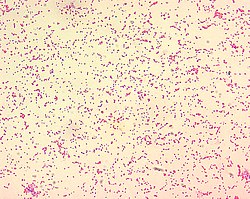

Chorobę wywołują bakterie z rodzaju Brucella. Są to gramujemne pałeczki, nieposiadające rzęsek, ani otoczek, niewytwarzające przetrwalników bakterie tlenowe.